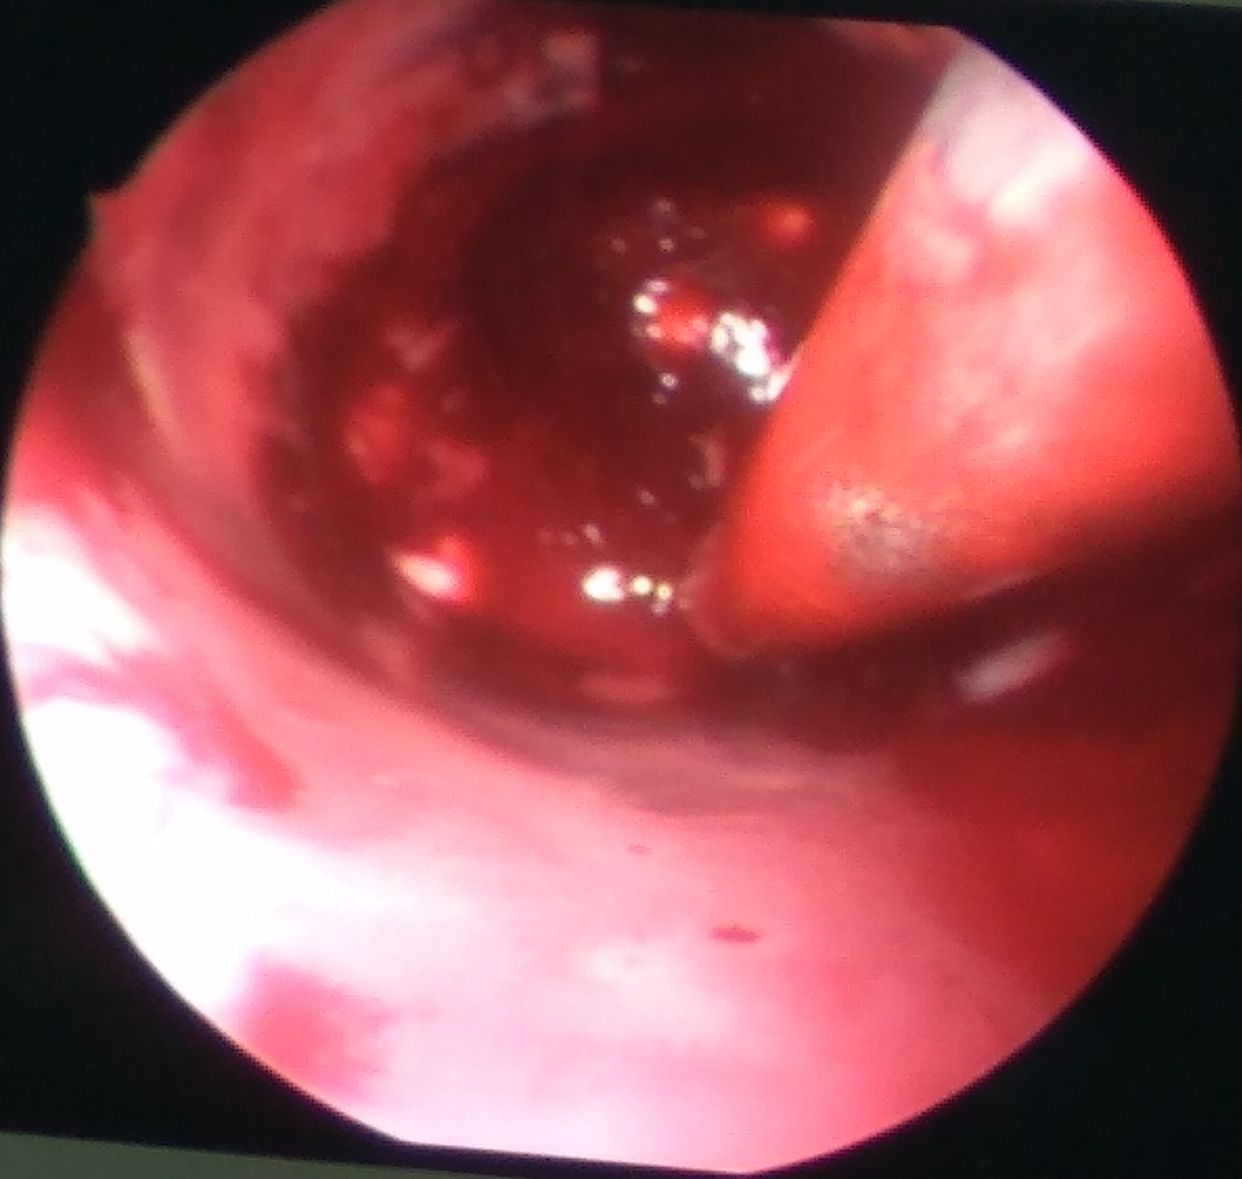

血肿偏外侧,清除完后血肿腔贴敷速即纱